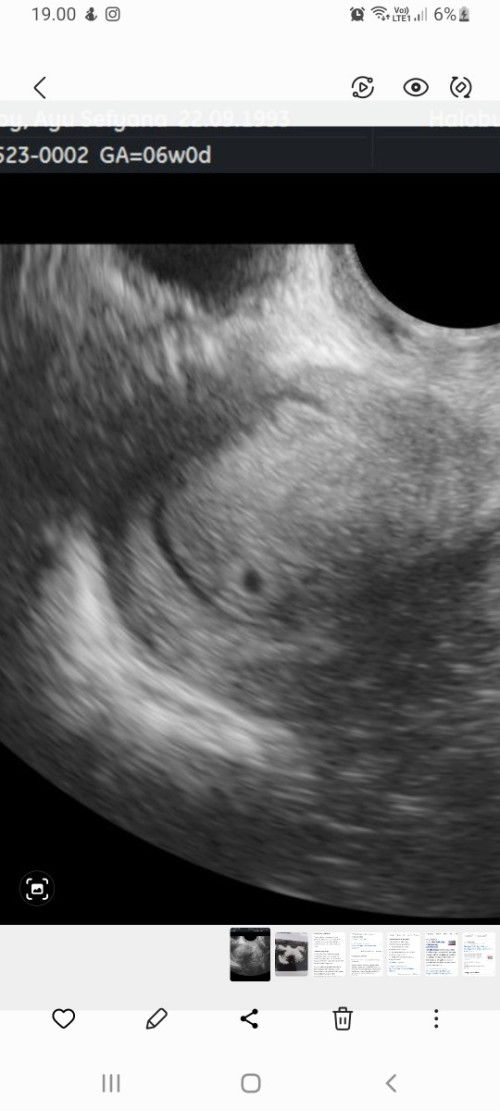

Usg 6w baru kantung kecil, normalkah?

Bun mohon pencerahannya, saya baru usg usia kandungan 6w hpht nya 10 April 2023, kata dokternya baru ada kantung rahimnya aja dan itu pun kecil bgt, normal ga ya? Janin mulai keliatan di week brp biasanya bun? Ini di kasih penguat rahim sama vitamin d3 #seriusnanya #bantusharing #firstmom #pleasehelp #firstbaby